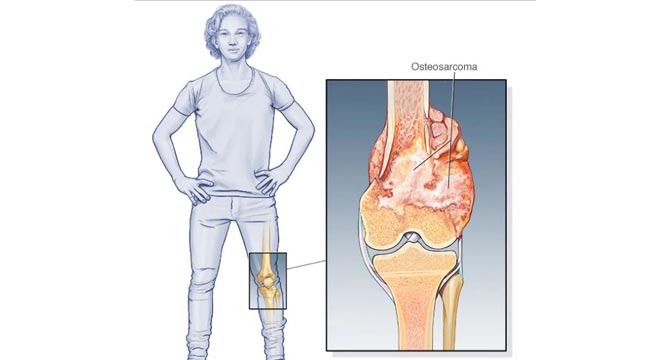

این سرطان در سنین زیر 20 سالگی رخ می دهد و احتمال ابتلاء به آن با افزایش سن کم می شود. درمان سرطان استخوان انتخاب روش درمان بستگی به نوع اندازه مرحله سرطان سن و سلامت عمومی بیمار دارد. سرطان استخوان چیست انواع سرطان استخوان. چشم انداز بهبود سرطان استخوانی بستگی به عواملی مانند سن نوع سرطان استخوان گستردگی سرطان مرحله و احتمال گسترش بیشتر آن درجه دارد به طور کلی در مورد سرطان استخوان بسیار ساده تر است که.

تشخیص سرطان استخوان. استئوسارکوم شایع ترین نوع است که بیشتر بر کودکان و نوجوانان زیر 20 سال تأثیر می گذارد. جراحی اغلب اولین انتخاب درمانی می باشد اگرچه گاهی اوقات قطع کردن عضو لازم می باشد. درمان سرطان استخوان به نوع سرطان بستگی دارد.